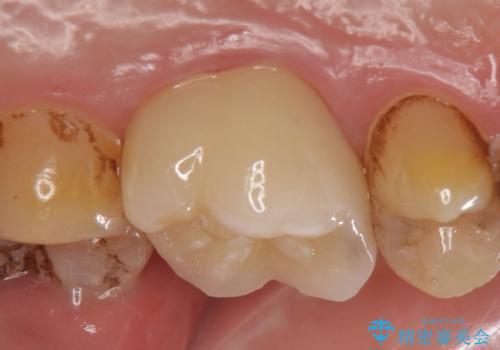

今回用いたオールセラミッククラウンは、ジルコニアフレームという白い素材の上にセラミックを盛っているため審美性が非常に高いのが特徴です。

またジルコニアは人工ダイヤモンドの材料にも使われているほど高い強度を持っており、そのためオールセラミッククラウンは審美性だけでなく、奥歯やブリッジの補綴も可能なクラウンです。